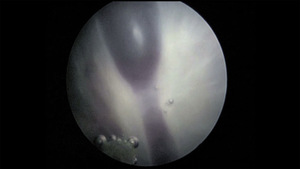

Od ukończenia 16 do ukończenia 26 tygodnia ciąży optymalne jest leczenie przyczynowe, czyli fotokoagulacja naczyń łączących lub zamknięcie pępowiny jednego z płodów, ewentualnie wspomagane farmakoterapią (glikozydy naparstnicy, steroidy, tokoliza). Po ukończeniu 26 tygodni ciąży uważa się, że czas do osiągnięcia przez płody dużych szans na przeżycie i prawidłowy rozwój po urodzeniu jest już na tyle krótki, a ryzyko związane z fetoskopią na tyle duże, że proponuje się leczenie objawowe. Stosuje się wówczas amnioredukcje seryjne, które zmniejszają skłonność do czynności skurczowej i porodu przedwczesnego, albo indometacynę lub sulindak, zmniejszające w sposób nieinwazyjny objętość płynu owodniowego u biorcy. Daje to czas na stymulację dojrzewania płuc płodów steroidami i przygotowanie pacjentki do porodu. Jeśli obserwowane są cechy niewydolności krążenia u biorcy, można również podać pacjentce glikozydy naparstnicy.1,5,9

Przed wprowadzeniem do leczenia fetoskopowej laserowej koagulacji naczyń łączących (ryc. 2), również w II trymestrze ciąży wykonywano seryjne amnioredukcje. Pozwalało to istotnie przedłużyć czas trwania ciąży, ale ze względu na objawowy charakter tej metody nie hamowało postępu zmian hemodynamicznych u płodów. Prowadziło to stosunkowo często do trwałych uszkodzeń ośrodkowego układu nerwowego (OUN) i nieprawidłowego rozwoju psychoruchowego dzieci. Laseroterapia została porównana do seryjnych amnioredukcji w wielu pracach, ale niewiele z nich sięga obserwacją poza 28 dzień życia dzieci.10-12